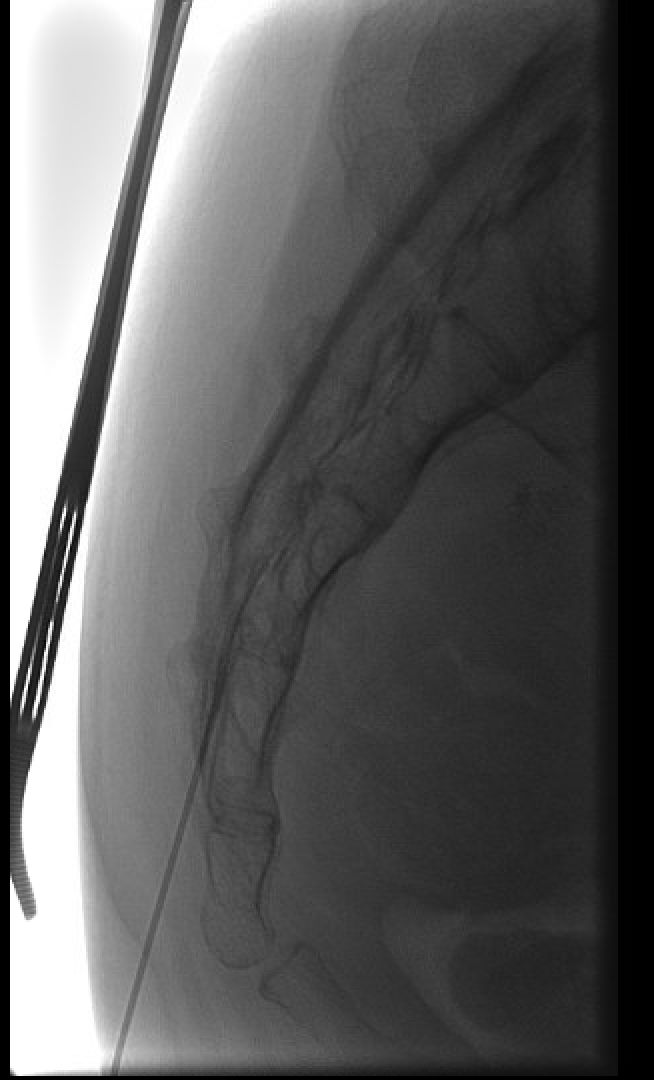

Interlaminar needle placement under fluoroscopy — paramedian approach through the ligamentum flavum at L4–L5 or L5–S1 interspace.Contrast test showing the characteristic epidural spread pattern — tracking bilaterally around the dural sac and along exiting nerve root sleeves. Confirms correct placement prior to steroid injection.

Transforaminal (TFESI) Technique

The "Scotty dog" view on oblique fluoroscopy — pedicle is the eye, transverse process the nose, superior articular process the ear, inferior articular process the foreleg. Needle target is the "6 o'clock" position of the pedicle (eye).

Oblique fluoroscopy to visualize "Scotty dog" at target level — pedicle is the eye; transverse process the nose; superior articular process the ear; inferior articular process the foreleg.

Needle target: "6 o'clock" position of the pedicle (safe triangle) — inferolateral to the pedicle and above the exiting nerve root.

Advance 22 G or 25 G spinal needle toward the target under oblique guidance; rotate to AP and lateral to confirm depth (needle tip at mid-pedicle depth on lateral).

CRITICAL: live digital subtraction angiography (DSA) with contrast test — 1–2 mL iodinated contrast under DSA to identify inadvertent intravascular uptake (rapid washout, linear filling) or intrathecal filling (dural sac fill). Any vascular uptake — reposition and retest.

Epidural confirmation: contrast tracks along the nerve root sleeve and into the anterior epidural space.

Inject non-particulate steroid (dexamethasone 10 mg) + 1–2 mL anesthetic (lidocaine or bupivacaine) slowly.

Transforaminal needle positioned at the "6 o'clock" position of the pedicle (safe triangle) — inferolateral to the pedicle and superior to the exiting nerve root.Transforaminal contrast spread along the exiting nerve root sleeve and into the anterior epidural space — confirms epidural placement prior to non-particulate steroid injection.